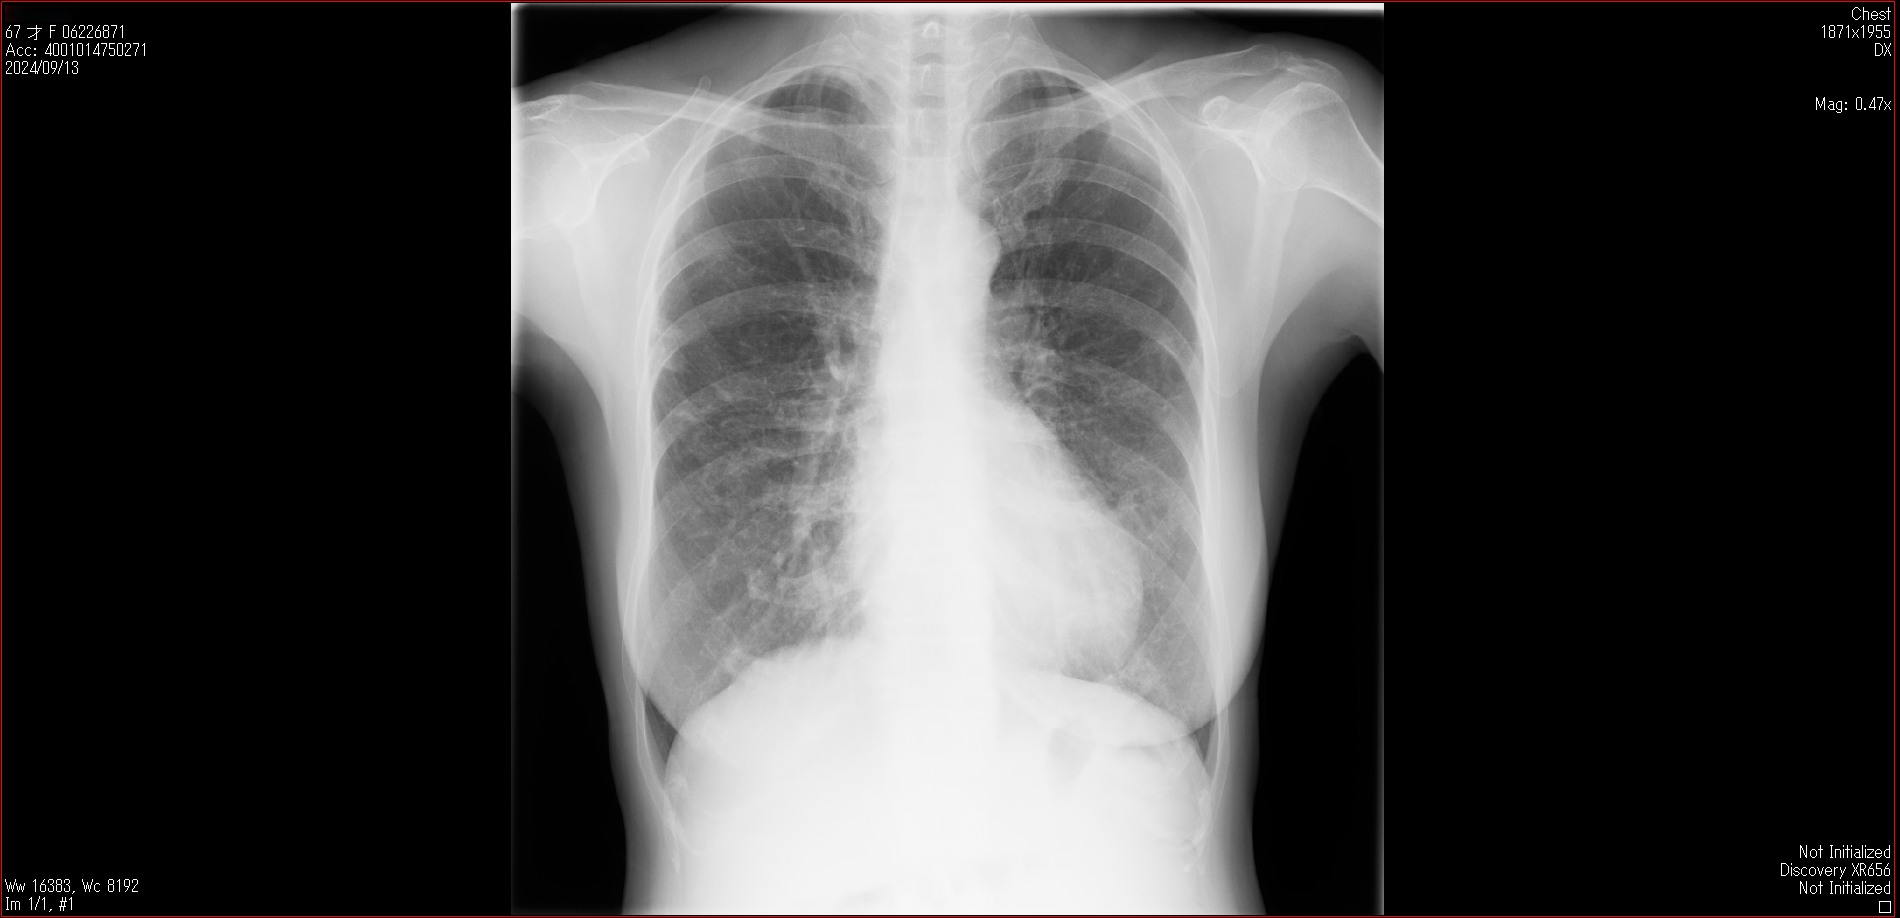

肺X線画像

- 2024.09.13 転院後の要観察(3)(私立の病院Z)